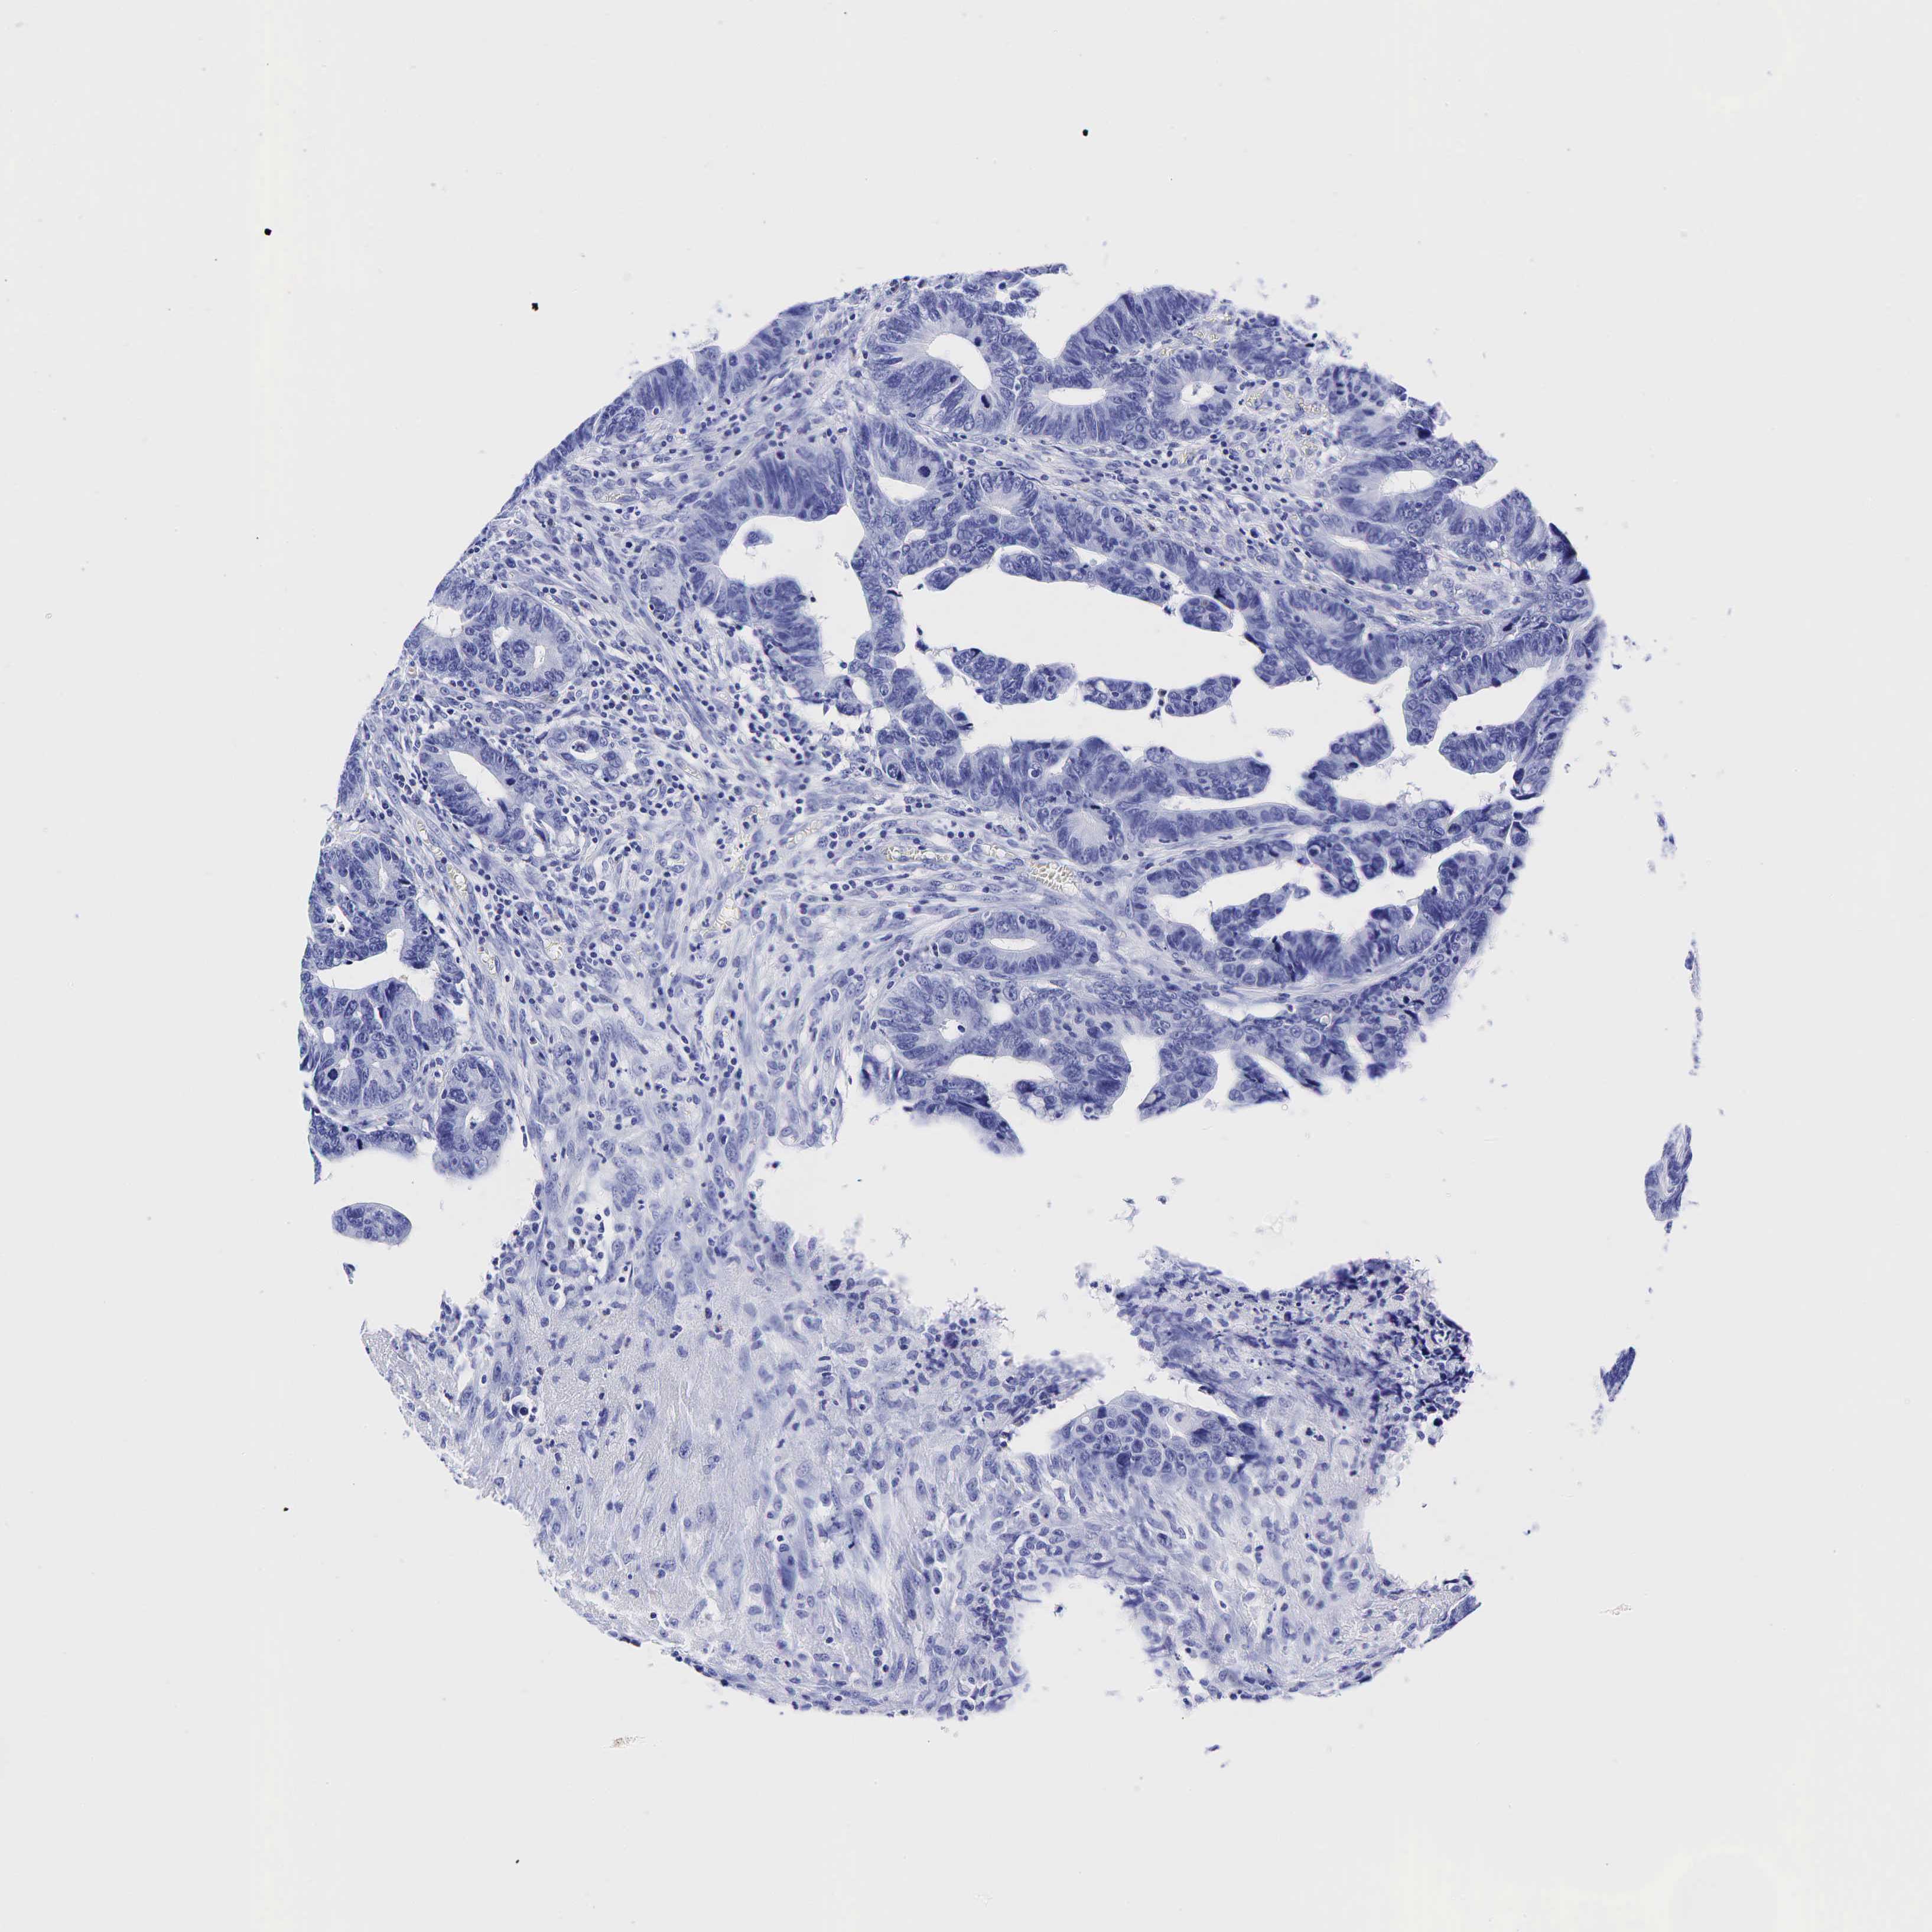

CANCER COLORECTAL CANCER Show tissue menu

Colorectal cancer

Human cancer

Colon adenocarcinoma

Rectum adenocarcinoma